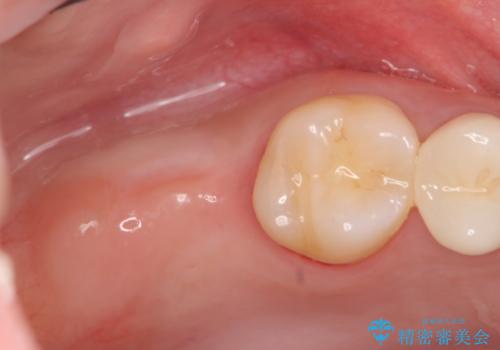

今回下顎の欠損部位はブリッジも検討されましたが、並行性の観点から最後方臼歯の神経を取るリスクを抑えるためインプラント治療を選択しました。